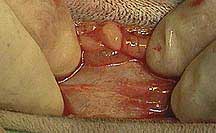

The tear in the abdominal muscles was 4 inches long. It can be visualized here as the horizontal opening towards the bottom of this picture, just under Dr. P’s finger. A large segment of the small intestines was found caught in this hole, and was gently removed just prior to this picture.

Intestines do not belong in this area, and are easily damaged when trapped in an opening this size, especially for 5 days in this case. In this picture Dr. P is carefully checking them to make sure their blood supply in intact.